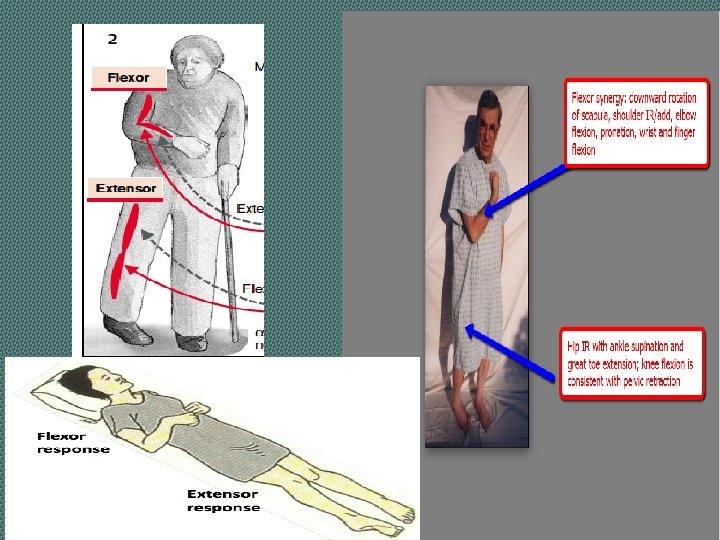

Weakness And Loss Of Skilled Movement Ø A unilateral pyramidal lesion above the decussation in the medulla causes weakness of the opposite limbs. Ø When acute and complete, this weakness will be immediate and total, a hemiplegia, e. g. following an internal capsule infarct. Ø With slowly progressive lesions (e. g. a hemisphere glioma) a characteristic pattern of weakness emerges – a hemiparesis. Ø There is also loss of skilled movement – fine finger and toe control diminishes.

Changes In Tone And Tendon Reflexes Ø An acute lesion of one pyramidal tract (e. g. internal capsule stroke) causes initially FLACCID paralysis with loss of tendon reflexes. Ø Increase in tone follows, usually within several days due to loss of inhibitory effects of the corticospinal pathways and an increase in spinal reflex activity. Ø SPASTICITY is characterized by sudden changing resistance to passive movement – the clasp-knife effect. Ø Relevant TENDON REFLEXES become exaggerated; Ø CLONUS may emerge.

Changes In Superficial Reflexes Abdominal (and cremasteric) reflexes are abolished on the side affected. The Babinski sign.

Clinical Features of Stroke § SIGNS: § § § § PULSE: Irregular (At. Fib), Slow (Raised ICP) BP: High Unconciouness Pupils: Small or Dilated EYES: Devited towards on side (conjugate gaze) Cranial Nerves may be involved Dysphasia, Dysarthria Initially limbs may be flaccid with absent reflexes (Spinal Shock). This may persist for days, weeks or months and then Classical UMNL signs develop

Clinical Features of Stroke § SIGNS: Hemiplegic weakness of upper limb affects the shoulder abductor, elbow extensors, wrist and finger extensors and small musles of hand Hemiplegic weakness of lower limb affects hip flexors, knee flexors and dorsiflexors and evertors of the foot